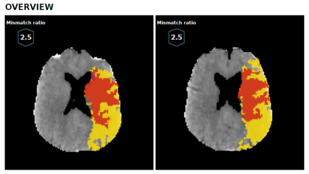

Všichni pacienti s podezřením na cévní mozkovou příhodu projdou ve FN Ostrava vyšetřením na CT. Vyšetření ale zejména u cévních mozkových příhod, které se staly před více než 6 hodinami, nedokáže naprosto přesně určit rozsah tkáně, která je postižená. Po provedení CT perfuze pak software bezpečně barevně ukáže místa, která zasažená nebyla- ta jsou šedá, červeně zabarví část mozku, kterou už se obnovit nepodaří a žlutá barva pak ukáže tkáň, která je poškozená jen částečně a dá se obnovit. Podle velikosti zasažené části se pak tým lékařů rozhodne, k jakému typu léčby přistoupí.